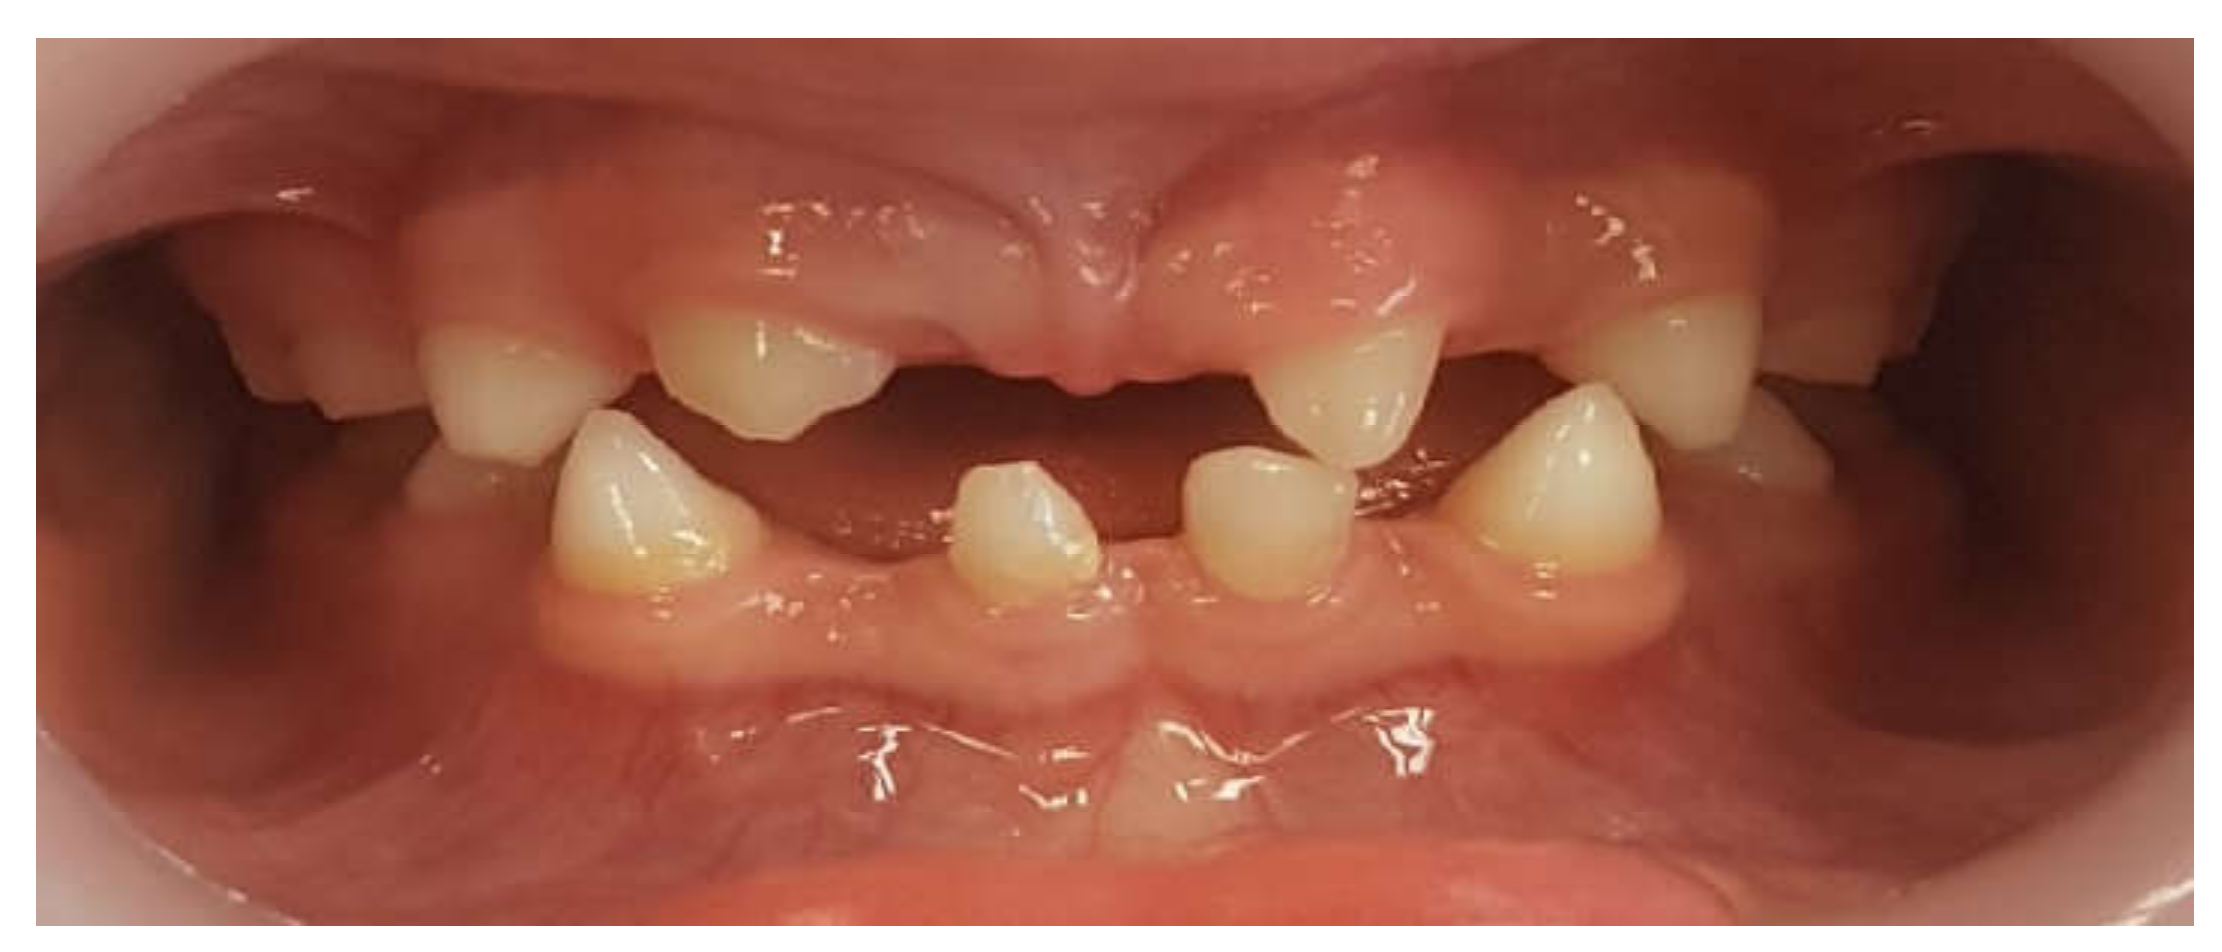

Primary Teeth Supported Fixed Prosthesis—A Predictable Treatment Alternative